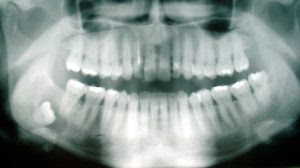

Did you know that wisdom teeth are the final remaining permanent teeth to emerge in your mouth? These tin can begin to erupt usually anytime effectually the age of 18, merely can also remain dormant and may never appear. And for some people, they can grow in perfectly fine, calculation 4 more molars to consummate their adult teeth.

Wisdom Teeth Coming In | Signs & SymptomsIn general, wisdom teeth serve no specific purpose, other than existence an additional pair of molars on each side of the mouth to aid in grinding food. Yet, due to their tardily eruption (usually between the ages of 17 and 24), these four additional teeth can get problematic in instance they don't have enough room to emerge.

Wisdom teeth are the last set of your 32 teeth to push through the gums. If their placement is proficient and the alignment is right, they are not probable to cause whatsoever issues. In this case, a wisdom molar does non need to exist removed.

Still, often, wisdom molar begins to come in sideways. In case of the lack of space, it can remain trapped under the gum line, disrupting the alignment of other teeth. This wisdom tooth is "impacted" and may develop cysts or tumours, which can destroy the jaw bone and cause molar decay if left untreated.